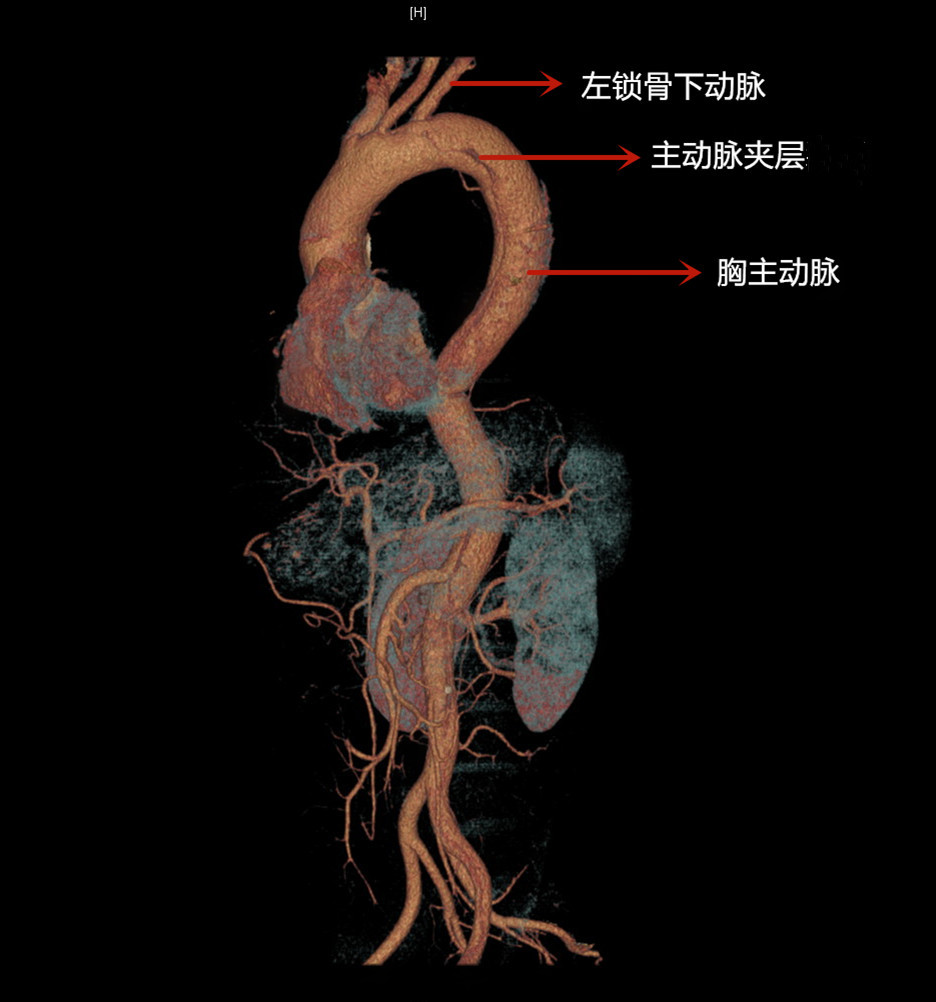

血管重建图像

6月5日,崔先生总觉得后背疼,“像是有什么东西被撕裂开了”,疼痛感加重后赶忙来到清华大学附属北京清华长庚医院急诊。急诊内科医师马士程接诊后,了解到崔先生有多年不规律治疗的高血压、糖尿病史,结合症状,在排除急性心梗后高度怀疑为夹层动脉瘤。经完善主动脉造影(CTA)检查,果然证实了猜测——Stanford B型主动脉夹层。夹层蜿蜒曲折,像一条游龙潜在主动脉上,延伸到髂动脉。